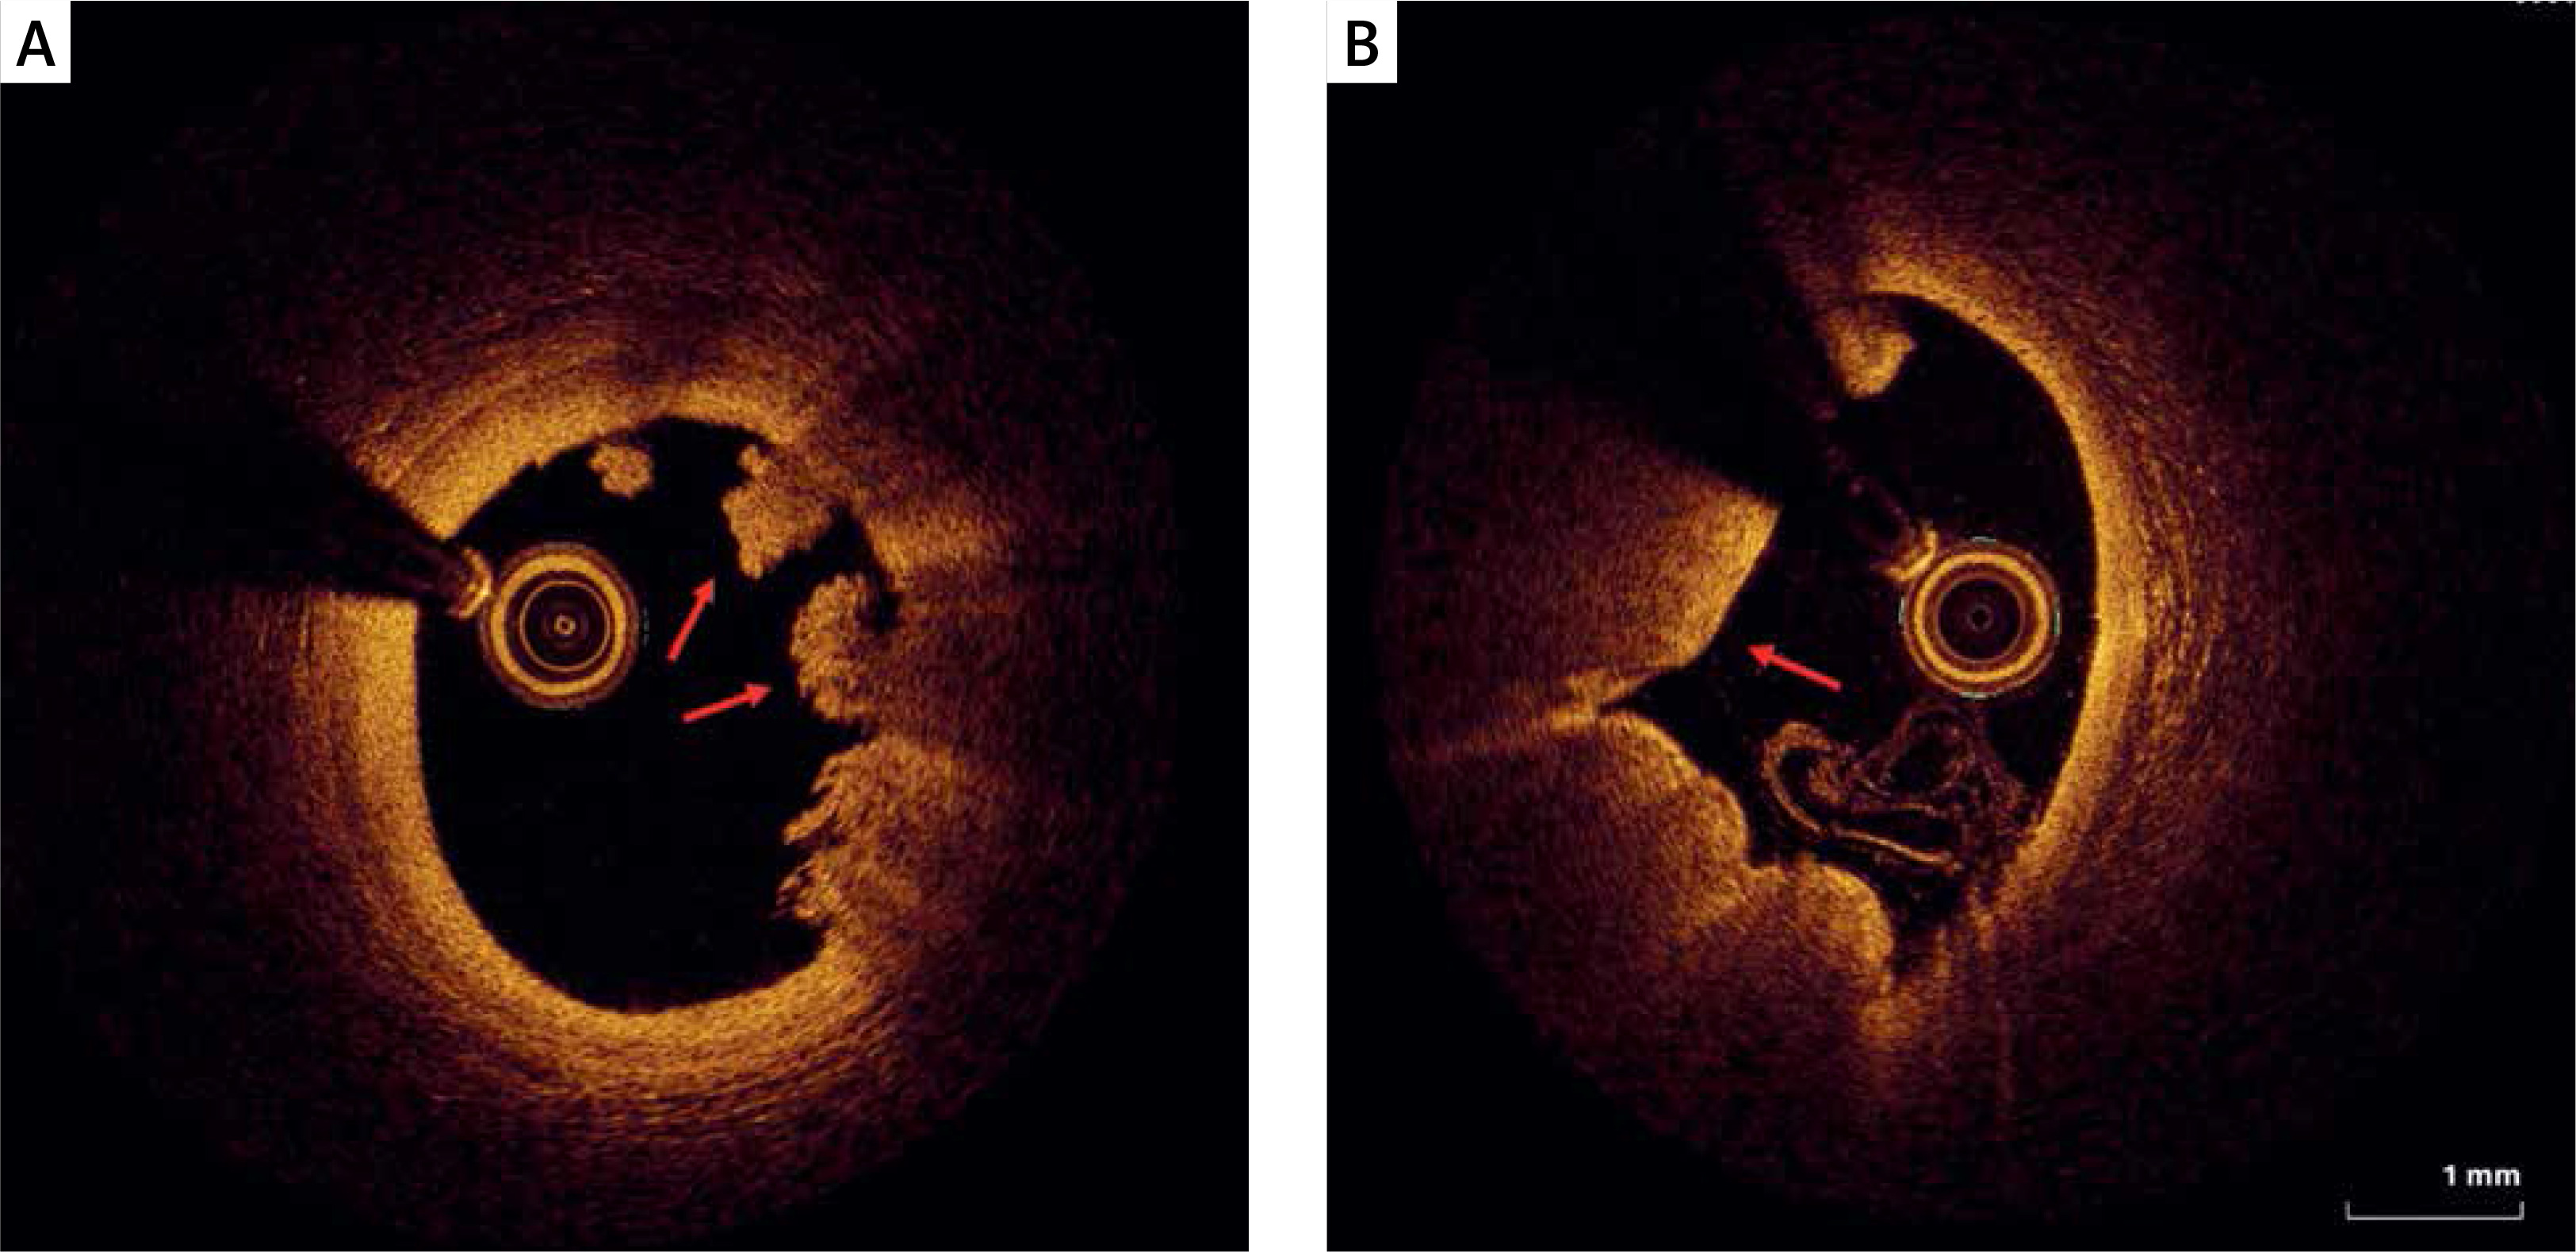

Figure 4

Eruptive calcific nodules (OCT). A, B – Nodular calcification protruding into the lumen through a disrupted thin fibrous cap (asterisk)